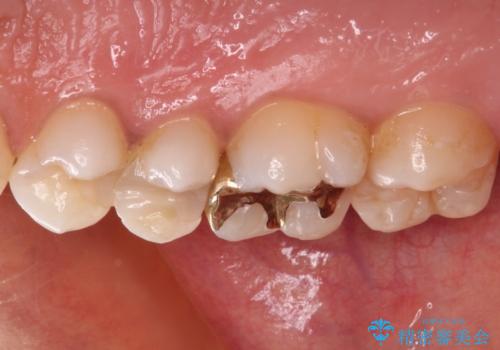

奥歯のむし歯をゴールドインレーで修復

- 奥歯にフロスが引っかかるようになり、虫歯ではないかとのことで来院された患者様です。

レントゲン写真より、左右奥歯にむし歯があることが分かりました。

奥で目立たないことから、虫歯の再発リスクが最も低く、咬合力による歯への負担も少ないゴールドインレー(PGAインレー、白金加金インレー)にて修復治療をすることとしました。

ゴールドインレーは銀歯のインレーやセラミックインレーと比べ、「技工操作の精度が高く、適合が著しく良い」というメリットがあります。特に上の奥歯は歯科医師の操作が行いにくいため、「適合の良さ」は再治療のリスクを防ぐ上でとても重要な要素となります。